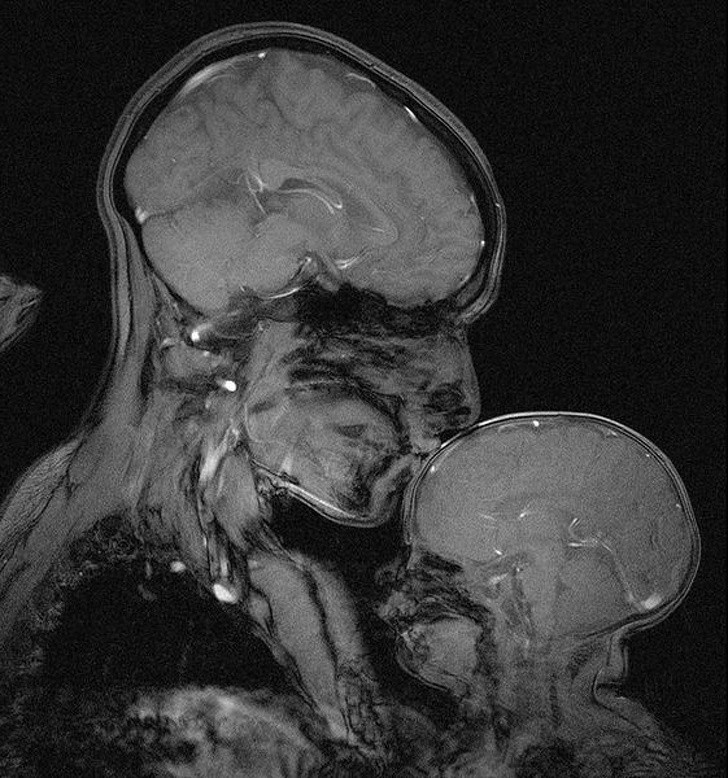

5. Kobieta z dzieckiem na zdjęciu rentgenowskim

Kobieta z dzieckiem na zdjęciu rentgenowskim